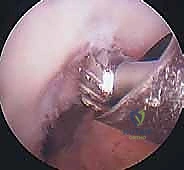

الخطوة الأولى: الفحص بالمنظار الجراحي 4K

يستخدم الدكتور